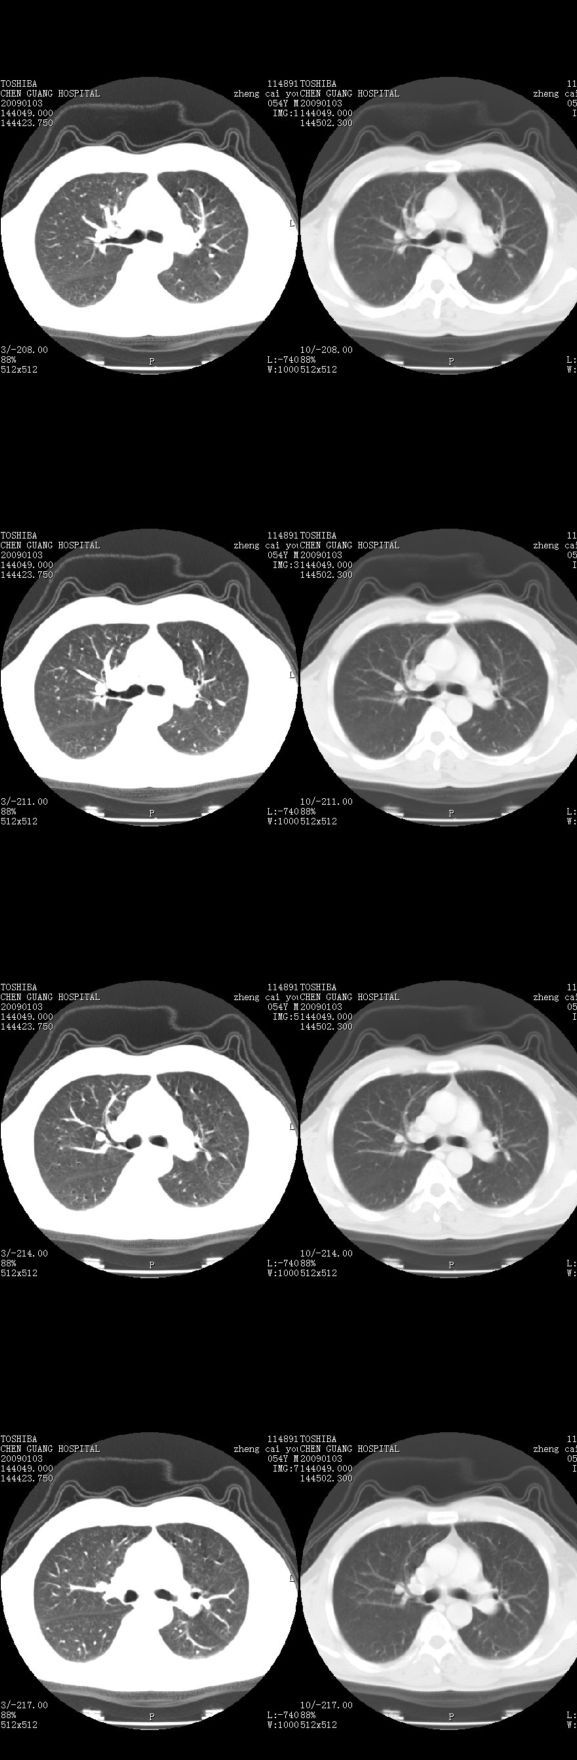

男,54岁,平时有吸烟后咳嗽、咯痰史,因右侧胸部(腋窝下)疼痛来检查平片,见右下肺动脉干起始处处结节,后到同学处做了平扫及增强。请各位老师帮忙看一下,不甚感谢!!!!!

多为血管断面影;建议必要时行ct增强扫描检查。

没有纵膈窗,也没有增强,确实不好说。从连续层面来看像是血管影。不放心做个强化最好了,毕竟是自己最亲的人!!

增强了 但纵隔窗调的看不清  右上叶支气管壁似有增厚 警惕

肺窗薄扫、常规扫描均未见明确病变;右下肺门圆形与肺血管等密度影,考虑为血管变异;应该要纵隔窗才能进一步明辨。

主要应该看一下纵隔窗,感觉到右肺门的血管有局限性的扩张,呈结节状,再做个增强ct扫描.